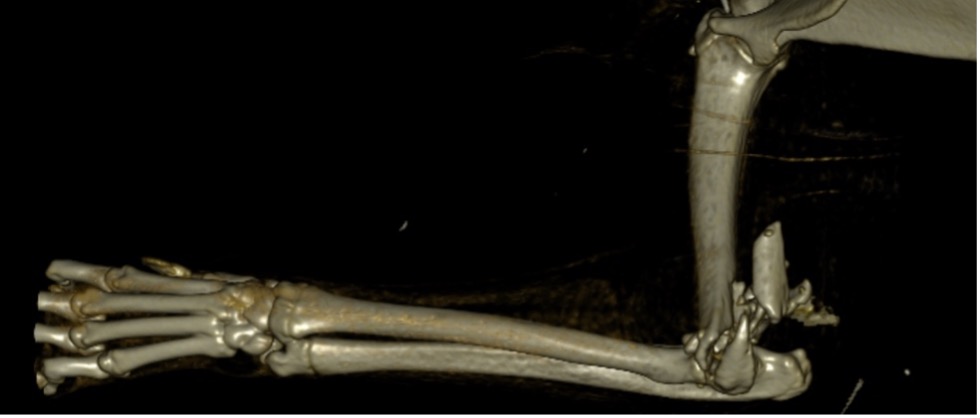

L’avènement récent des plaques anatomiques constitue une nouvelle option dans le traitement de ces fractures : dans l’exemple 3 (chat Ragdoll), une plaque anatomique médiale de 2 mm acceptant des vis de 1,6 et 2 mm a été utilisée seule avec succès.

Figure 9 : Pré-Op

Figure 10 : Opération

Figure 11 : Post-Op Immédiat

Figure 12 : Post-Op 1 mois